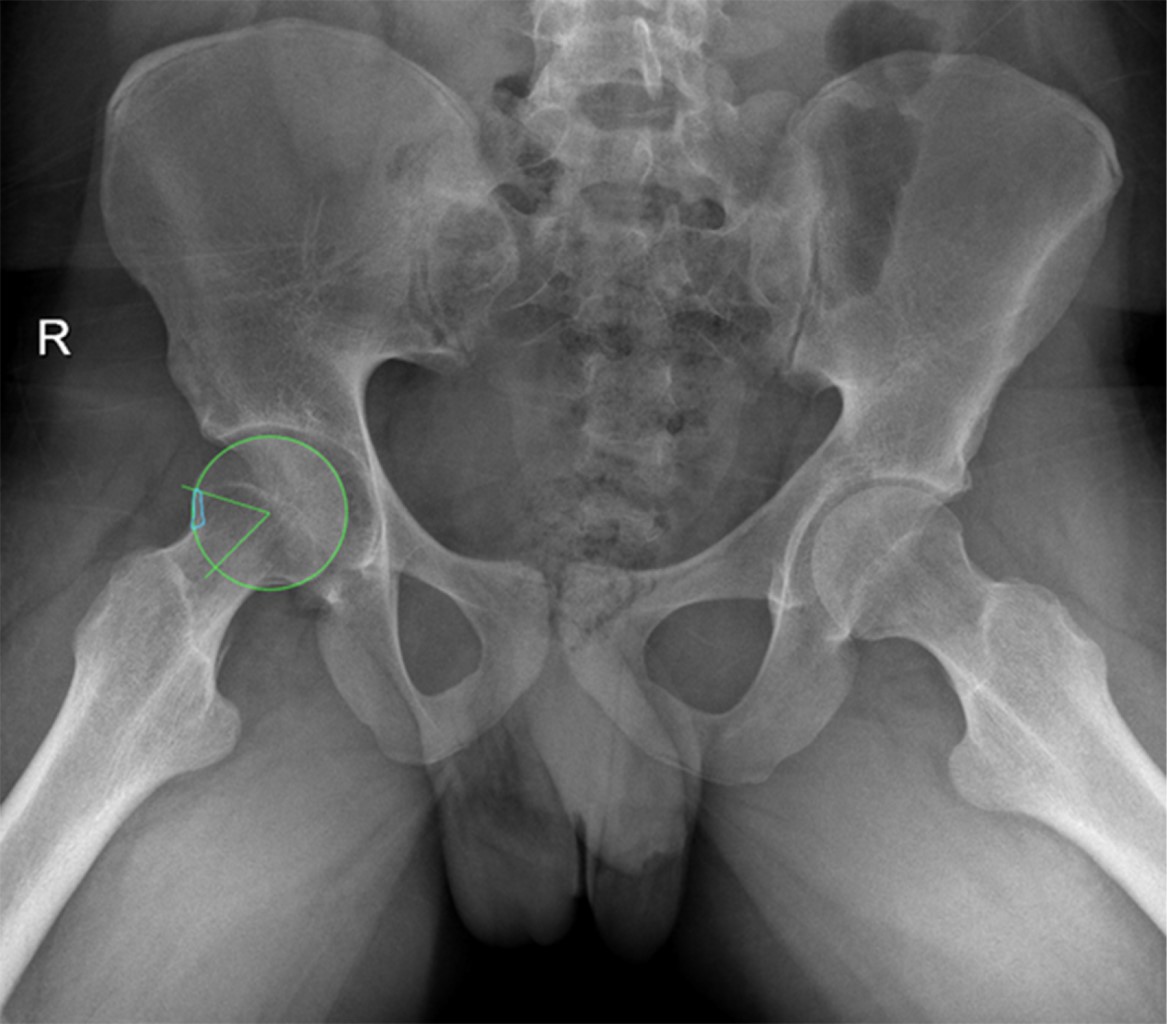

Figure 1

The painful hip has been a topic of study that has evolved from the beginning of the last century to the present. The clinical approach is complex, and requires a systematization process associated with good questioning, clinical maneuvers with their corresponding interpretation, and complementary imaging studies. The understanding of hip pathology, especially in young adults, is highly simplified and sometimes underdiagnosed, therefore, not treated in a timely manner. The prevalence of painful hip is more common in males (49 to 55%) than in females (25 to 28%), and the causes may vary according to demographic characteristics and the history of each patient. Bryan Kelly, made a topographic and anatomical description of the approach to the painful hip according to the theory or system of the layers: I. Osteochondral layer; II. Inert layer; III. Contractile layer; and IV. Neuro-mechanical layer. This system helps us understand the anatomical site of pain and its clinicopathological correlation. The semiological approach to hip pain is the fundamental pillar for differential diagnosis. We can divide it according to its topography into anterior, lateral and posterior, as well as according to its chronology and characteristics. The physical examination should be carried out systematically, starting from a generalized inspection of gait and posture to the evaluation of specific signs for alterations in each layer, which evoke pain with specific postures and ranges of mobility, or weakness and alterations in the arc of mobility of the joint. Image evaluation is initially recommended with radiographic projections that evaluate different planes, both coronal, sagittal and axial, complemented with panoramic views, and eventually dynamic sagittal ones if necessary. Requesting specific studies such as tomography to evaluate bone structure and reserve, or simple MRI when there is suspicion of soft tissue affection, or failing that, arthroresonance for joint pathology, will depend on the clinical symptoms and radiographic findings.